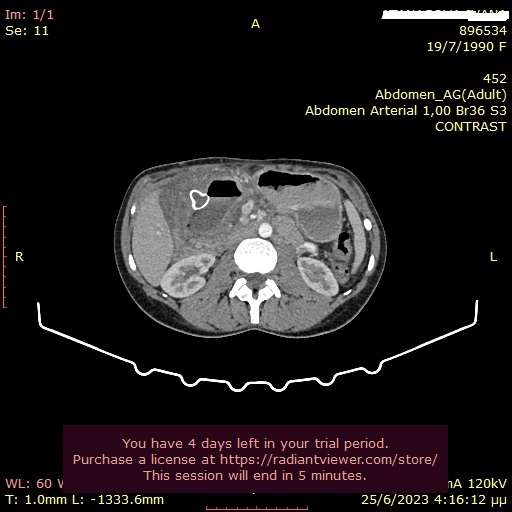

9) Παροχέτευση ψευδοκύστης παγκρέατος με την καθοδήγηση του ενδοσκοπικού υπερήχου και τοποθέτηση Hot Axios stent

Γυναίκα 33 ετών, με ιστορικό χειρουργικής παροχέτευσης ψευδοκύστης παγκρέατος προ 8ετίας, προσήλθε με κοιλιακό άλγος και εμέτους. Η αξονική τομογραφία κοιλίας έδειξε επανεμφάνιση μιας μεγάλης ψευδοκύστης με διάμετρο 11εκ στην περιοχή της παγκρεατικής κεφαλής, η οποία προκαλούσε πιεστικά φαινόμενα στο βολβό και τη 2η μοίρα του δωδεκαδακτύλου. Η κύστη περιείχε αρκετή ποσότητα υπερηχογενούς υλικού. Έγινε παροχέτευση της κύστης με τοποθέτηση LAMS (Hot Axios stent) 15x10χιλ από το δωδεκαδάκτυλο, με την καθοδήγηση του ενδοσκοπικού υπερήχου. Η όλη διαδικασία διήρκεσε 10 λεπτά και η ασθενής εξήλθε από την κλινική την επόμενη ημέρα. Σε επανέλεγχο μετά από 2 εβδομάδες η ψευδοκύστη είχε μικρύνει σε διάμετρο 3,3εκ. Το stent αφαιρέθηκε μετά από 5 συνολικά εβδομάδες χωρίς καμία επιπλοκή.

Ευμεγέθης ψευδοκύστη παγκρέατος

Υπερηχογραφική απεικόνιση του Hot Axios stent